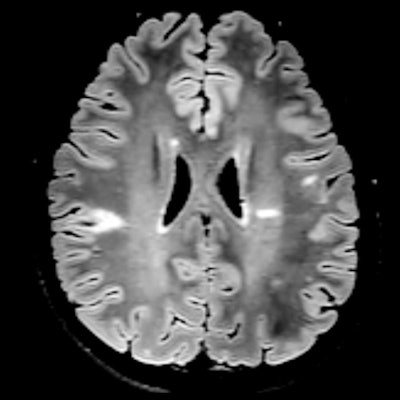

In particular, 3D fluid-attenuated inversion recovery (FLAIR), T2-weighted MRI, and contrast-enhanced MRI are among the best tools to definitively determine the presence of MS and to evaluate patients' response to drug treatments.

Multiple sclerosis lesions can appear anywhere in the central nervous system. As such, a definitive diagnosis of MS relies heavily on clinical observation by virtue of MRI and by identifying MS symptoms as they develop over time. Clinicians also need to look for lesions in other areas, such as the brain stem, cerebellum, ventricles, and cortical and intracortical regions.

The MR imaging sequences currently recommended to clinicians for MS are proton-density, T2-weighted, and 3D FLAIR in multiple planes, and, as needed, the accompaniment of a gadolinium-based contrast agent (GBCA). Given the promise of today's MRI hardware, images of MS can be acquired on most scanners in approximately five minutes, highlighted by isotropic resolution that allows for "reslicing" in multiple directions in approximately five minutes as well. Barkhof recommended T2-weighted imaging with gadolinium for an initial MRI MS scan and perhaps when the patient's treatment is changed.

In these circumstances, clinicians can use an abbreviated MRI protocol with 3D FLAIR, DWI, or T2-weighted imaging to screen for any signs or indications of PML in less than 10 minutes.